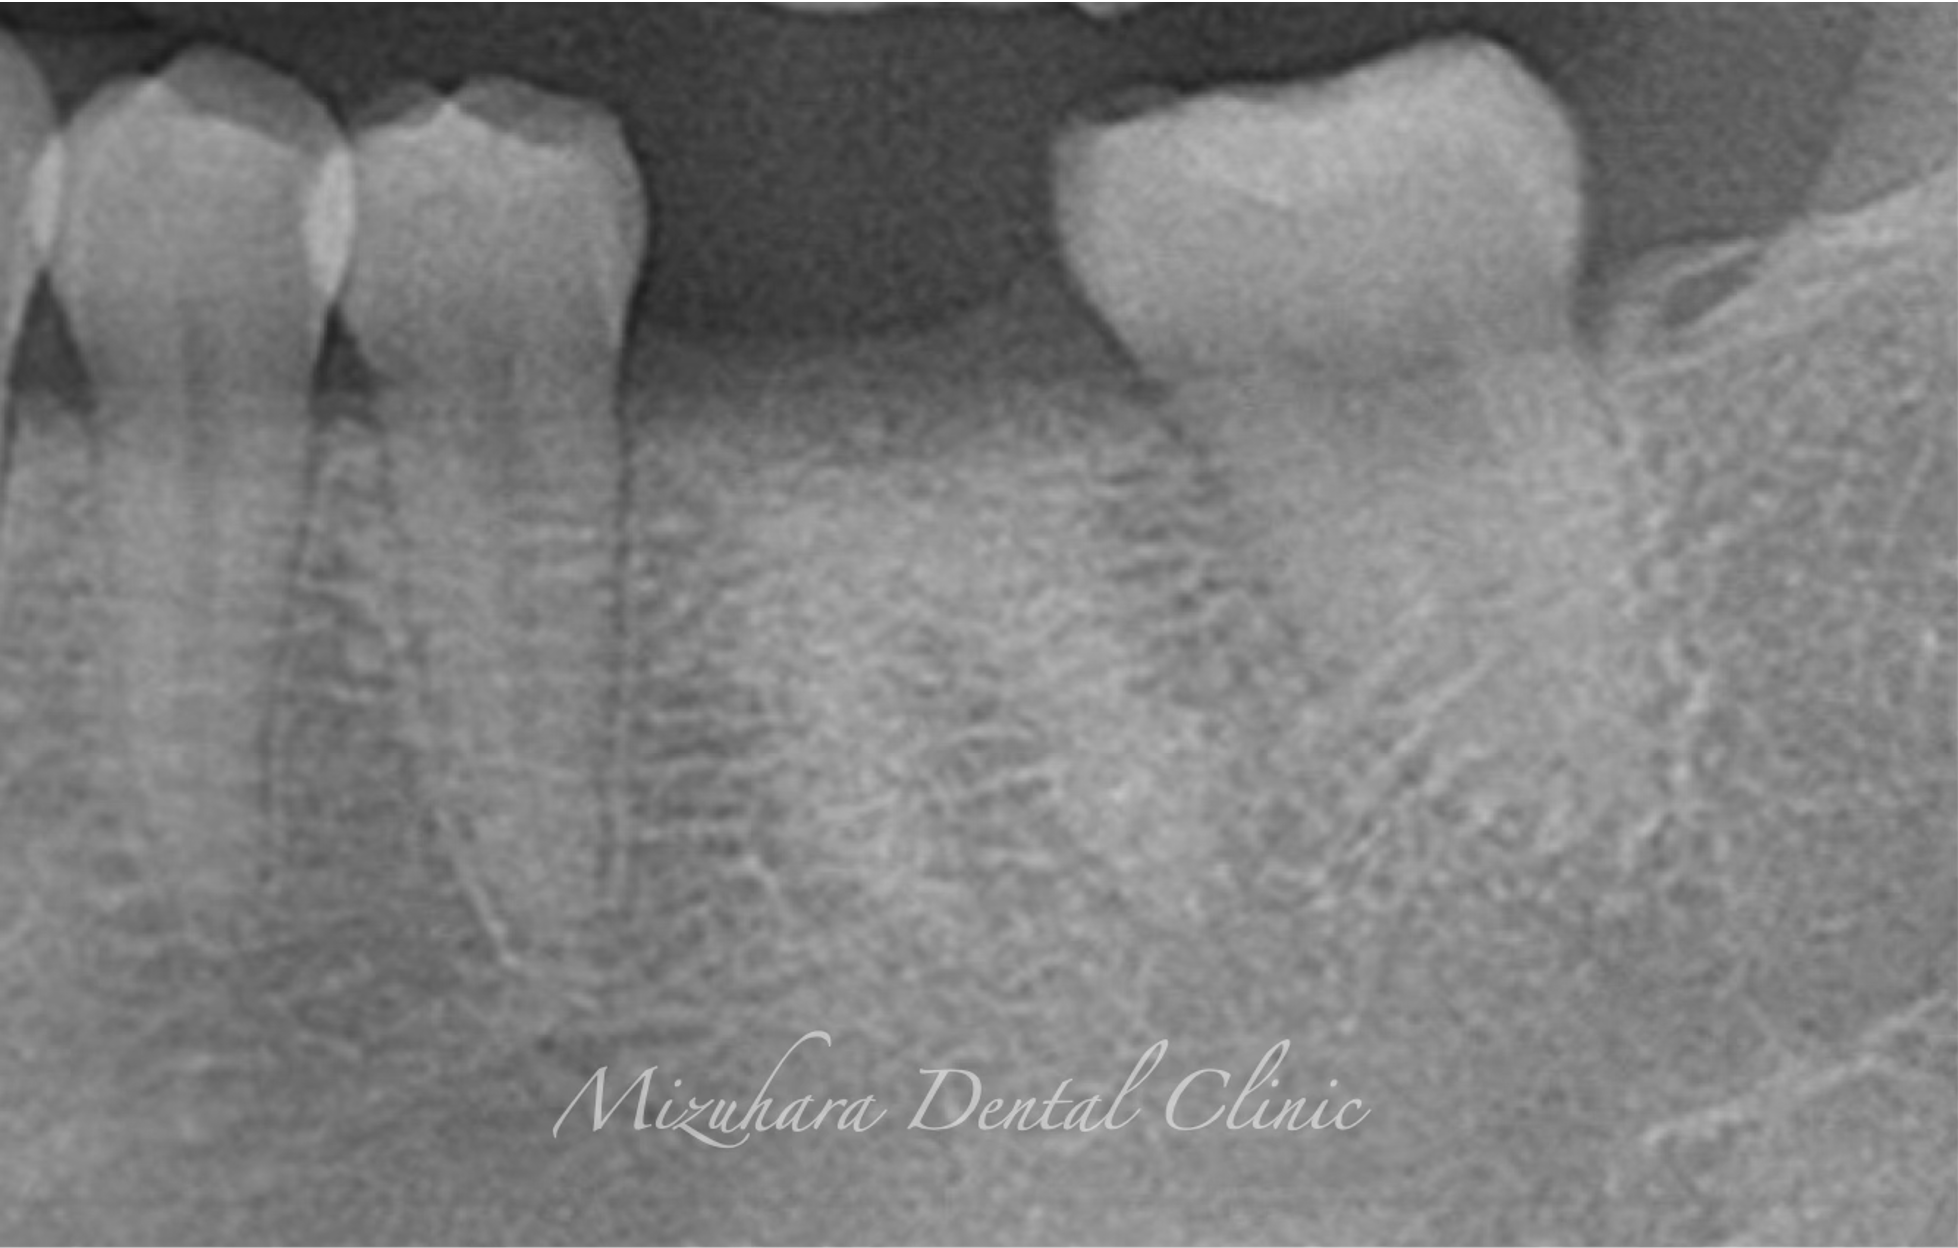

CASE

症例紹介

三鷹の歯医者【みずはら歯科・矯正歯科 三鷹】